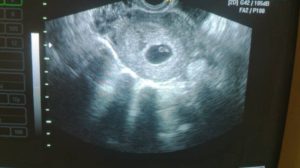

Беременность 6 недель может стать поводом для УЗИ, только если врач предполагает, что она многоплодная, либо у женщины были в анамнезе выкидыши и случаи внематочной беременности. В обычной ситуации в проведении ультразвукового обследования сейчас нет необходимости.

УЗИ обычно проводят трансвагинальным датчиком – на этом сроке данный способ более информативен. Будущая мама сможет услышать, как бьется сердечко ее малыша, увидеть его на экране монитора и на фото.

Врач делает выводы о расположении плодного яйца, его размерах и точном сроке беременности.

При обследовании может быть назначено УЗИ на 6 неделе беременности. На таком сроке УЗИ позволяет определить наличие плода в матке, то есть, исключить внематочную беременность. Можно увидеть, сколько плодных мешочков начали свое развитие в матке, то есть, выявит многоплодную беременность.

На таком сроке плод мало напоминает ребенка, эмбрион выглядит, как зернышко фасоли, да и его размер напоминает зернышко. Но зато при проведении УЗИ можно будет увидеть сердцебиение плода.

УЗИ на шестой неделе беременности помогает оценить наличие развивающейся беременности, врач использует трансвагинальный датчик из-за того, что он дает более четкие данные.

При ультразвуковом обследовании увеличивается размер матки, уже различаются отдельные части тела и органы плода. Можно прослушать сердцебиение малыша. На УЗИ до сих пор виден желточный мешок и желтое тело в яичнике.